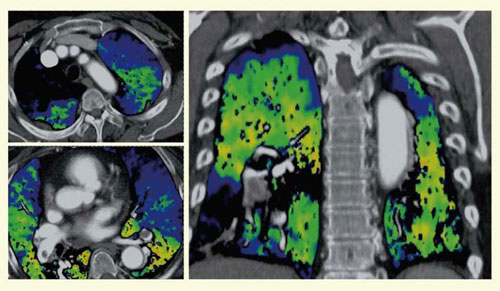

2)LungPBV(perfused blood volume)

肺野領域においても,各ボクセルの造影剤量が灌流血液量(blood volume)に相当するため,造影剤濃度から肺灌流血液量マップ(perfused blood volume map)が作成できる。肺塞栓症などの評価に有用であり,肺シンチグラムの代替検査としての可能性も示唆されている(図5)。

図5 肺塞栓症のLungPBV